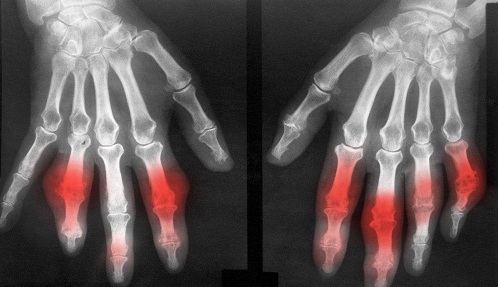

导读: 痛风主要表现为关节的剧痛,常常为单侧性突然发生。关节周围组织有肿胀、发热、发红和压痛,一般作血尿酸检查可以确诊。但因症状不够,早期多误诊为类风湿关节炎、滑囊炎、化脓性关节炎、急性蜂窝组织炎等。

导读: 痛风症状主要表现是存在痛风石,慢性关节炎、尿酸结石和痛风性肾炎及并发症。此时痛风频繁发作,身体部位开始出现痛风石,随着时间的延长痛风石逐步变大。